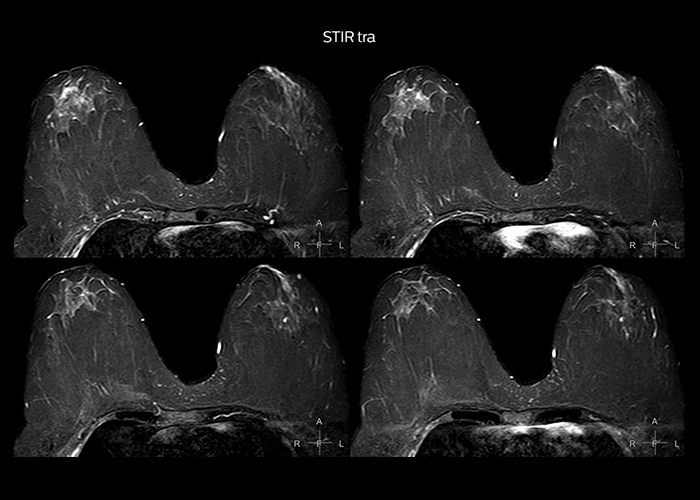

“On average, we scan about 80 patients per day, but on some days we scan well over 100 patients. The scanner is in use 7 days per week, operated 20 hours per day on week days and 8 hours per day in the weekend,” Mr. Tuna says. “To avoid coil changes we plan examinations of similar anatomies back to back, such as head and spine. Multiva helps us here a lot because coils don’t need to be changed frequently. Moreover, thanks to parallel imaging technology and 16-channel HeadSpineTorso and 8-channel MSK coils we are able to achieve excellent image quality. In this way Multiva helped us to increase both image quality and productivity.” “Neurological cases, such as brain and spine imaging, represent the largest share in our MR scanning, followed by musculoskeletal cases. In general, we use simple and basic imaging protocols. But occasionally, we use advanced techniques for problematic cases if necessary.